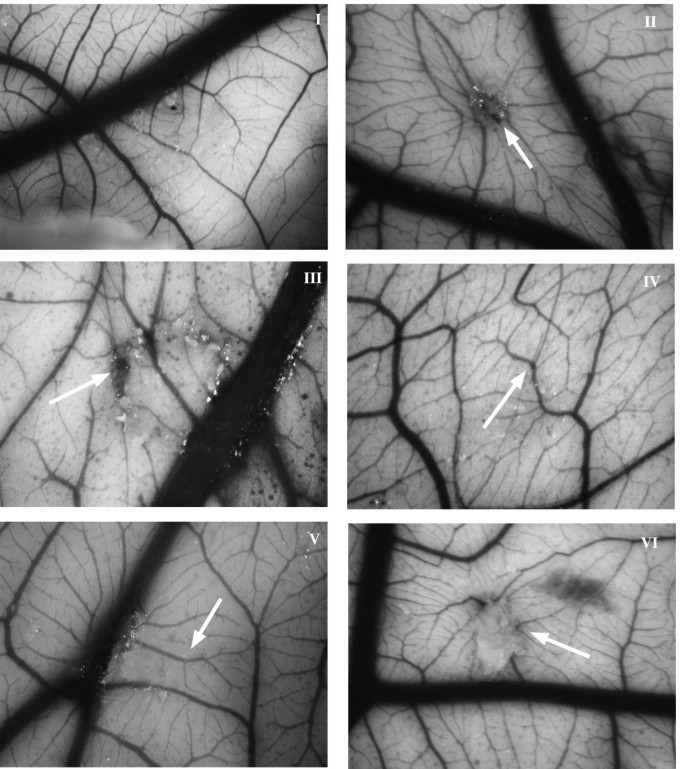

方法细节:4日龄鸡胚开窗,8日龄时在CAM上放置含化合物(10 μg)与FGF-2(100 ng)的甲基纤维素 pellet,14日龄时评分血管生成程度(0=无血管,3=强放射状血管)。

结果解读:FGF-2可诱导显著血管生成(评分m=3,n=15,p<0.001);compound 1完全抑制FGF-2诱导的血管生成(m=0,n=8,p<0.0001),compound 2抑制90%(m=1,n=5,p=0.0186);两种化合物单独使用均无炎症或血管生成活性。